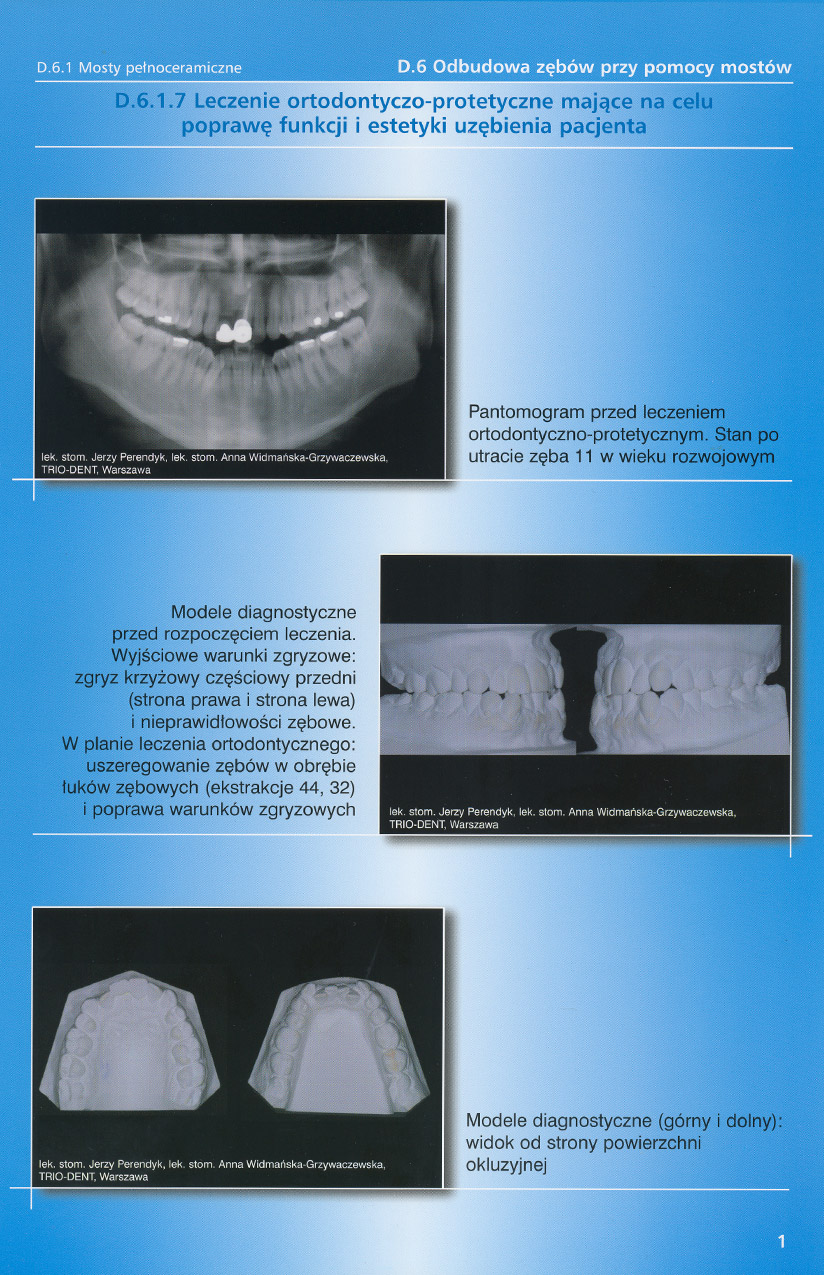

zobacz więcejGaleria przypadków klinicznych, obrazująca proces terapeutyczny od stanu wyjściowego aż do oddania ostatecznej pracy uzupełnienia brakującego uzębienia.